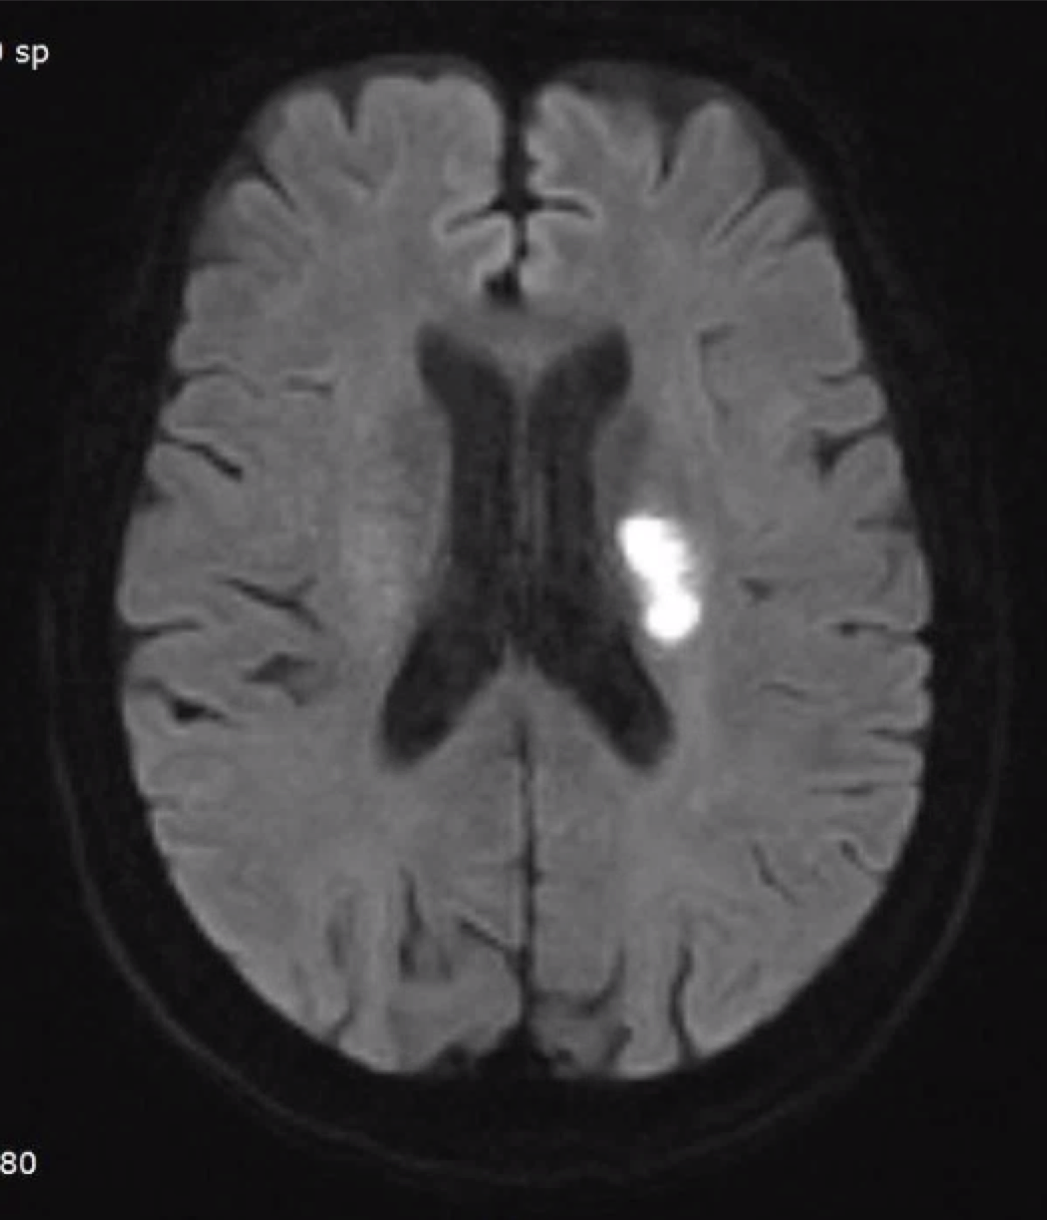

right hemiplegia d/t left BG, CR infarction 2019.8.8.